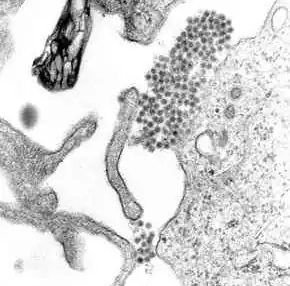

A transmission electron microscopy image showing dengue virus

A TEM micrograph showing dengue virus virions (the cluster of dark dots near the center)

Dengue virus (DENV) is an RNA virus of the family Flaviviridae; genus Flavivirus. Other members of the same genus include yellow fever virus, West Nile virus, and Zika virus. Dengue virus genome (genetic material) contains about 11,000 nucleotide bases, which code for the three structural protein molecules (C, prM and E) that form the virus particle and seven other protein molecules that are required for replication of the virus.[30][31] There are four confirmed strains of the virus, called serotypes, referred to as DENV-1, DENV-2, DENV-3 and DENV-4. The distinctions between the serotypes are based on their antigenicity.[32]